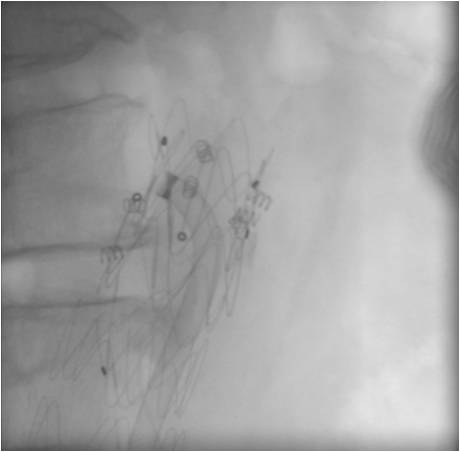

As seen from the presented table, eliminating type I EL required individual approach in all cases. Only in 4 cases the implantation of aortic cuff was performed in the isolated form to eliminate EL (Figure 1). In these cases, the aortic cuff was additionally fixed with Aptus EndoAnchors (Figure 2). In all cases, the procedure for EL elimination was confirmed with the intraoperative angiography, as well as by CT angiography or duplex ultrasonography with contrast enhancement after the surgery. No fatal outcomes were recorded.

Fig. 1. CT angiography after implantation of the aortic cuff in Ia type endoleak. Note: CT — Computed Tomography.